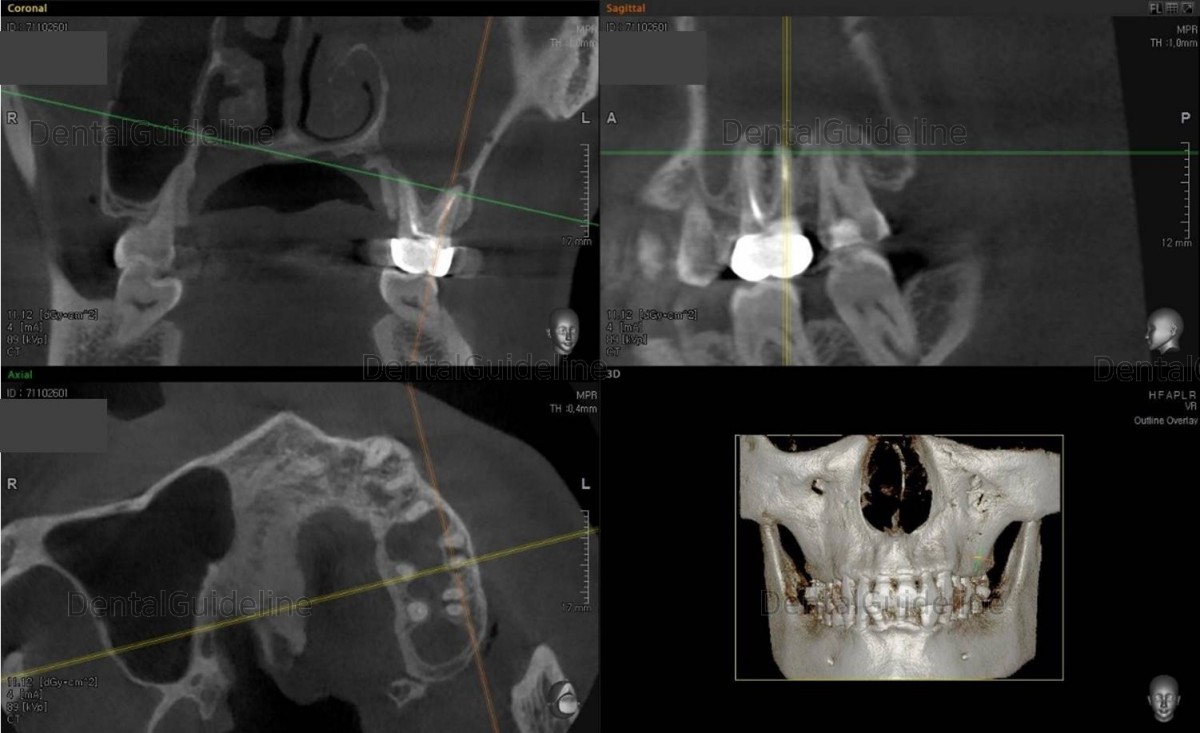

12, CBCT immediately after maxillary sinus graft.